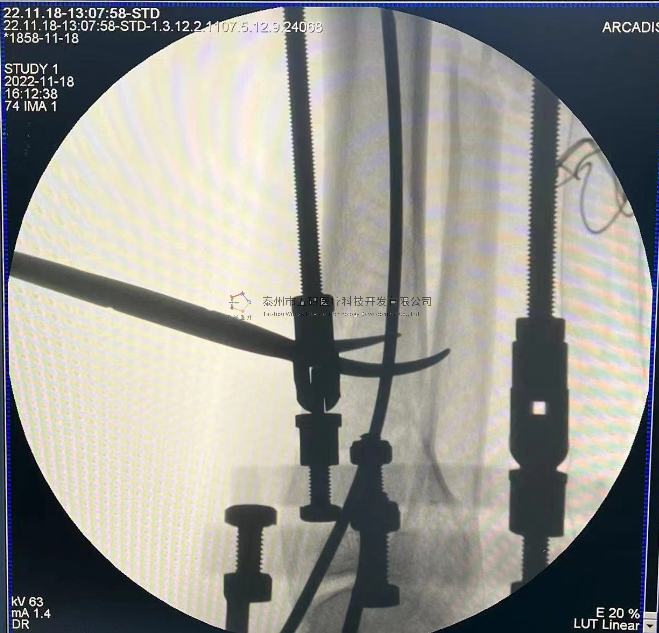

【治療后影像】

7.png

【手術(shù)資料】

8.png